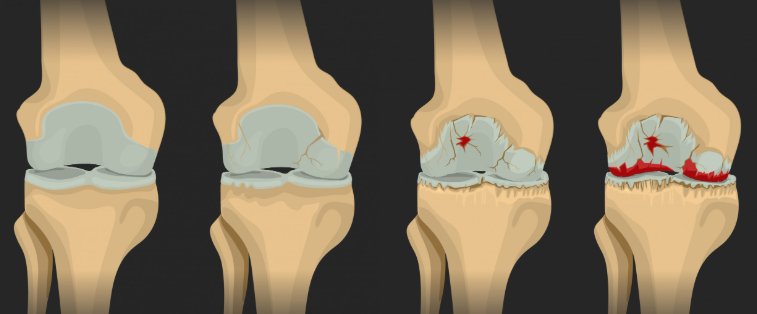

골관절염(Osteoarthritis)은 관절의 연골이 마모되거나 손상되어 발생하는 퇴행성 관절 질환입니다. 관절의 연골은 뼈와 뼈 사이에 위치하여 충격을 흡수하고, 원활한 움직임을 도와줍니다. 그러나 시간이 지나면서 연골이 닳아 없어지는 골관절염은 관절 주변의 뼈, 인대, 관절막 등에도 영향을 미쳐 통증, 기능 장애, 관절 변형을 초래할 수 있습니다.

- 관절 변형 : 시간이 지나면서 관절 모양이 변형되며, 기능을 잃게 됩니다.